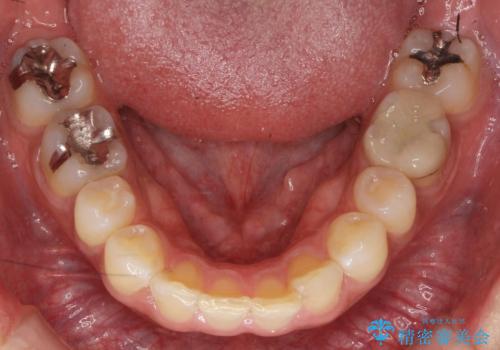

- 前歯だけ歯並びを治したいとのご希望で来院された患者様です。

数年前にワイヤー矯正を行ったものの、少し後戻りしてしまったそうです。

上の前歯が斜めに見えること、犬歯と小臼歯の間の隙間、上下顎前歯のがたつきを治すことをご希望されていました。

気になるのは前歯だけで、奥歯の咬み合わせは気にならないとのことでした。

ご予算と患者様のご希望により、インビザライン・ライト(マウスピース14枚)によるマウスピース矯正を行いました。